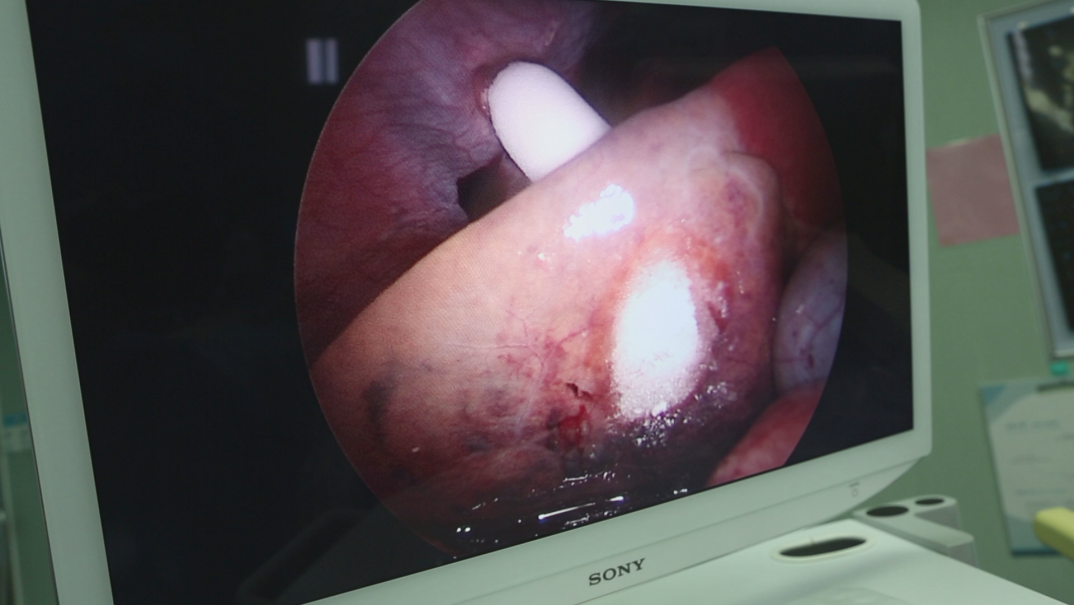

另一位患者陈先生之前因胃口不好,体型出现了明显消瘦,下降达10公斤,去了医院进行CT检查,被确诊为肝癌,大小约7公分。由于肿瘤贴近胃壁,直接手术切除存在很大风险,陈先生夫妇选择广州复大的纳米刀消融治疗,效果良好。

▲经过纳米刀的治疗,肝部的肿瘤得到很好的消融

纳米刀消融治疗是一种非热能的新型肿瘤微创消融技术。它消融时间短,治疗彻底,不易损伤大血管、胆管、神经等重要组织。其治疗区域通过细胞吞噬作用清除凋亡组织,促进正常组织的再生与修复,较少引起炎症反应,对复杂的病情有独特的优势。肝脏是各种恶性肿瘤发生转移的主要靶器官。结直肠癌患者在确诊时已合并肝转移的约占15%~25%,而原发灶根治术后发生肝转移的约占15%~25%,肝转移也是结直肠癌患者最主要的死亡原因。